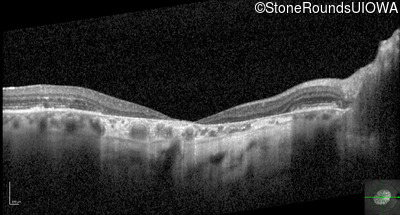

Optical Coherence Tomography - Right - 20/160 -1

Exemplar / OCT Stack

OCT Stack